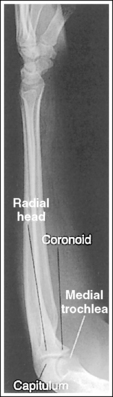

The capitulum-radius joint is either partially or completely closed, and the radial head articulating surface is demonstrated. The olecranon process is situated within the olecranon fossa, and the coronoid process is visible on end.

• The anatomical relationships of the elbow on an AP forearm projection are slightly different from those on an AP elbow projection because of the difference in centering of the central ray. The central ray is placed directly over the elbow joint for an AP elbow projection but is centered distally to the elbow joint, at the midforearm, for an AP forearm projection. With distal centering, diverged rays record the elbow joint image instead of straight central rays, much the same as if the central ray were angled toward the elbow joint. Imaging the elbow with diverged rays projects the radial head into the capitulum-radius joint and causes the anterior margin of the radial head to project beyond the posterior margin, demonstrating its articulating surface.

The distal humerus is in a lateral projection. The distal humerus demonstrates three concentric (having the same center) arcs, formed by the trochlear sulcus, capitulum, and medial aspect of the trochlea. The elbow joint space is open, and the radial head is superimposed over the coronoid process.

• A lateral proximal forearm projection is obtained by placing the elbow in a lateral projection and abducting the humerus until it is parallel with the IR, thereby putting the entire arm on the same horizontal plane. The wrist and hand are then placed in a lateral projection, and the medial (ulnar) aspect of the forearm rests against the IR (see Figure 4-64). Even though the capitulum is placed anterior to the medial trochlea and the humeral epicondyles are not superimposed for this position, an open joint space may still be obtained. Because the central ray is centered to the midforearm, the diverged x-rays used to image the distal humerus align parallel with the slant of the capitulum and medial trochlea (see Figure 4-63). The result of this parallelism is an open elbow joint space.